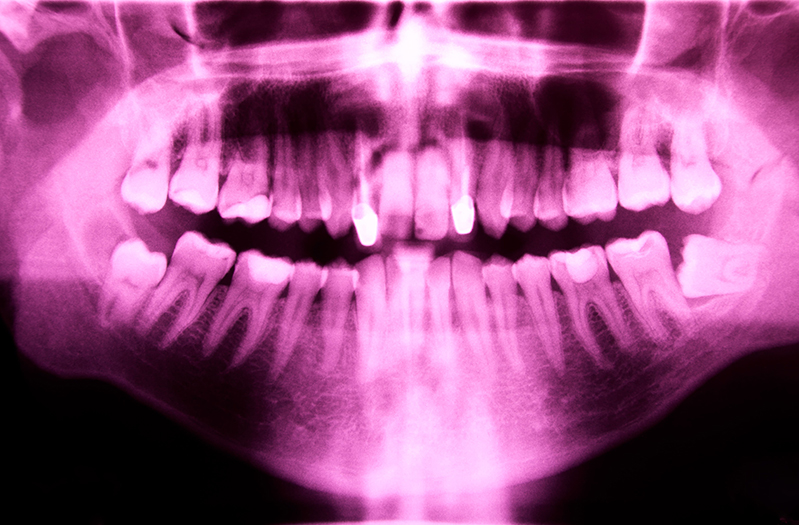

Many patients are not aware that periodontal maintenance is the only sure way to keep gum disease from returning. Periodontal maintenance is regularly performed at certain intervals after procedures such as scaling and root planing. Periodontal maintenance includes the removal of plaque and tartar, scaling and tooth planing and polishing. Your dentist will determine the frequency the periodontal maintenance is needed.

Gum disease, or periodontal disease, is initially treated with deep cleanings, also known as Scaling and Root Planing. Once all of the bacteria is removed and the tooth surfaces are made smooth, we then maintain your oral health with frequent checkups.

Another tool in our tool chest against gum disease. Gum disease affects the bony support around your teeth, creating deep pockets around the teeth for food to get caught in.